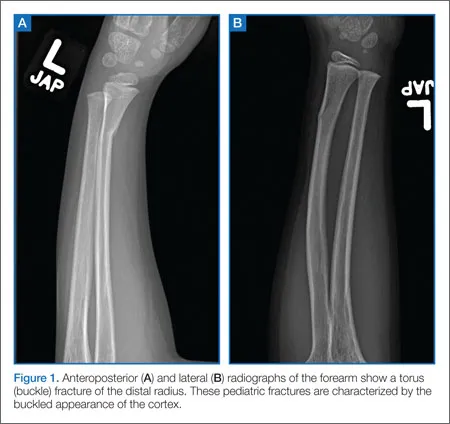

- Torus/Buckle: Compression failure of cortex, causing a bulge.

- Buckle (Torus): Stable; cast ~3 wks.

- Greenstick and torus (buckle) fractures are unique to children.